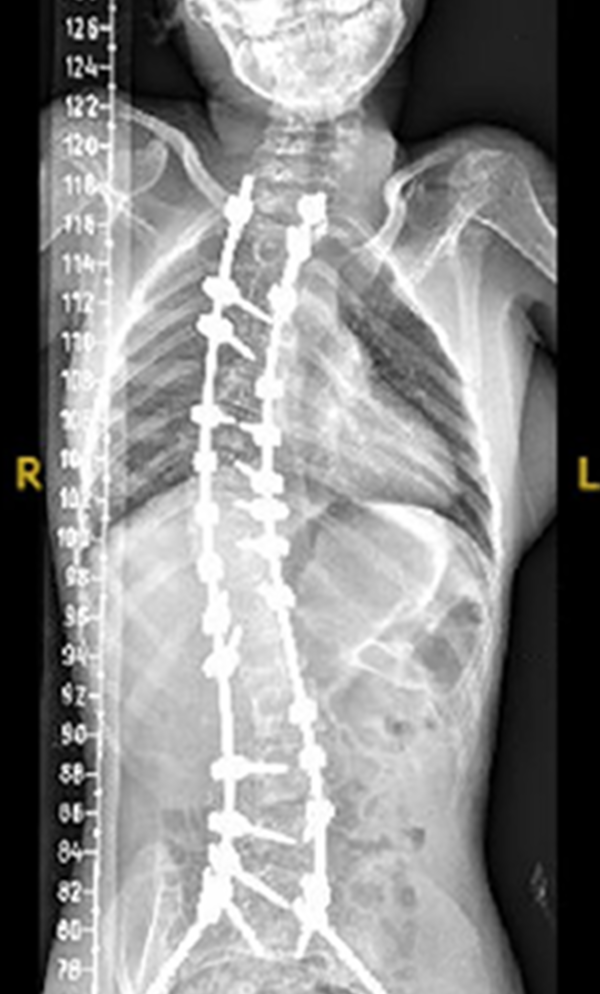

The procedure involves repositioning the spine and securing it with Screws and Rods. Bone graft is then placed so the treated vertebrae gradually heal together into one solid segment. This creates long-term stability, preventing further curve progression and improving overall alignment.

Rods are implanted along the spine to guide growth and assist in managing the curve. They can be lengthened non-invasively during follow-up visits using an external magnetic controller, reducing the need for repeated open surgeries for lengthening, with careful monitoring over time.

Gallery : Before - After

After

Before